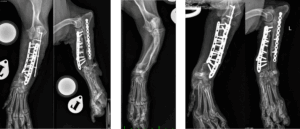

When the deformity causes pain, lameness, or significant misalignment, surgery—called a corrective osteotomy (one or more planned cuts) or a corrective ostectomy (removal of a small section of bone at a precise location)—may be recommended. The goal is to realign the bone into a straighter, more functional position and stabilize it, most often with a plate and screws sized for small animals (Figures 4–6).

- How the bone is stabilized: typically with a small‑animal plate and screws. In some cases, the ulna is also addressed to relieve tethering and reduce the chance of the deformity recurring.

- Why technology helps: modern locking plates and digital 3D planning with patient‑specific guides improve precision and efficiency.

- Rechecks: Scheduled visits and X‑rays confirm bone healing and implant position.